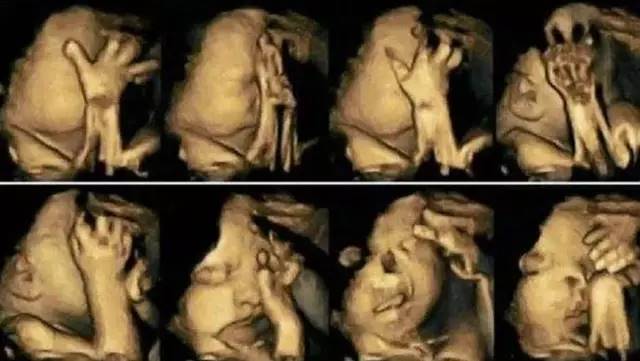

後來,通過超音波檢查,女子發現寶寶似乎個性非常活潑,在肚子裡不停翻身,一下子摸嘴巴,一下子又抓抓耳朵,甚至會摀著臉就像在哭泣一樣,逗得她開心直呼:「孩子會做鬼臉呢!將來一定很聰明!」

然而,站在一旁的醫生看完後,卻皺起眉頭,露出十分擔憂的表情,嘆了一口氣對準爸媽,「還是把孩子流掉吧!」他進一步解釋,「其實孩子看起來在笑,是因為有很嚴重的唇裂,從嘴巴一直裂到了耳朵,而以目前的醫學技術,根本就無法透過手術修復如此大的缺陷,所以還是別留了,生下來對他也是一種折磨。」